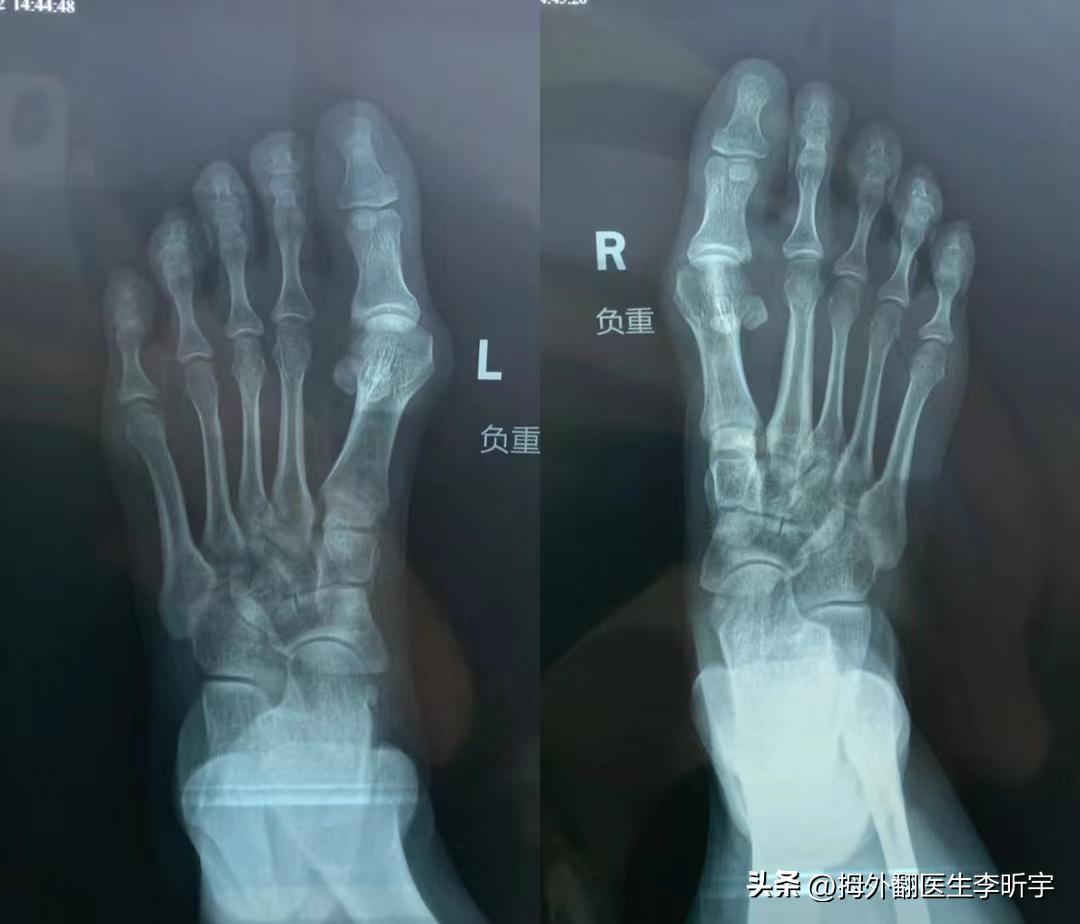

她说如果可以的话,她想要把两个大拇趾和两个小趾都做了。拍片一看小脚趾的骨头没有外翻,只是软组织过多,所以做两个拇趾就可以了。